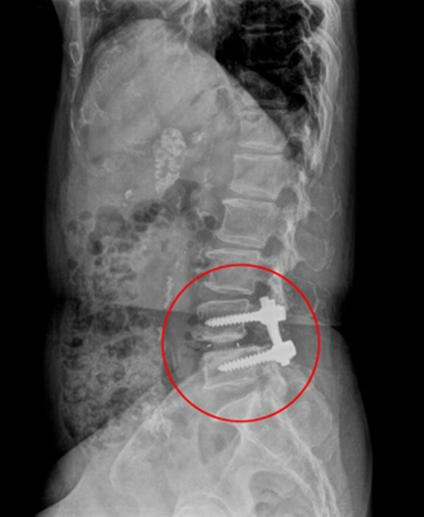

최소침습 척추고정술

척추고정술은 척추의 이상 정렬을 수정하고 고정하는 수술방법

이며 척추의 안정성을 회복시키고 통증을 완하하는데 도움을 줍니다.

주로 뼈의 고정이 필요한 경우 진행되며, 문제가 되는 병변 부위를 제거한 후 척추를 고정시킵니다. 디스크와 협착증의 재발 가능성을 차단하여 수술 후 만족도가 매우 높습니다

최소침습척추고정술 (수술전)

최소침습척추고정술 (수술후)